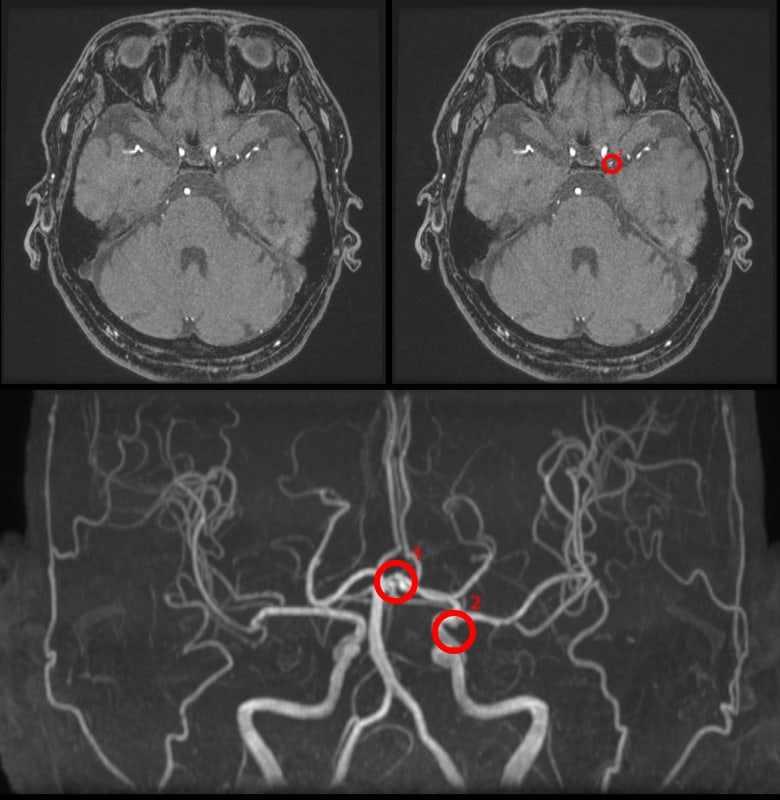

Diagnostic support for detecting brain aneurysms from brain MRA

Brain aneurysm detection support technology advanced from MRA

EIRL Aneurysm supports the interpretation process by identifying sac-like structures of aneurysms in brain MRA that are larger than 2 mm. The sensitivity of the doctor interpreting the images without the software was 68.2%. In comparison, the sensitivity with the assistance of the software was 77.2%, suggesting an improvement in diagnostic accuracy.